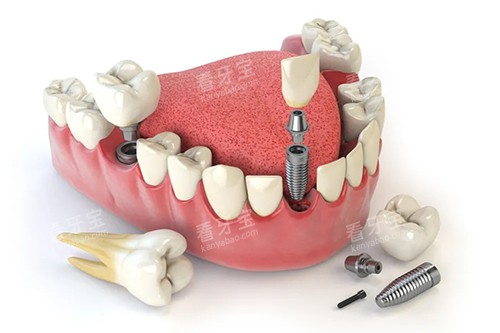

例如,在种植牙领域,医生们能够根据患者的口腔状况和身体条件,制定个性化的种植方案,确保种植结果的稳定性和美观性。

比如,智能化口腔全景机可以快速、清晰地拍摄口腔全景影像,让医生齐全了解患者的口腔结构;口腔CT则能够提供三维立体的口腔图像,为种植牙等复杂手术提供更好的术前规划。